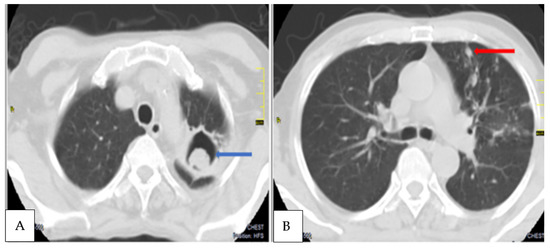

| 30 | M | Cough, haemoptysis, chest pain, weight loss | Positive | A. fumigatus, A. niger | Cavities, intracavitary material, pericavitary infiltration, pleural thickening adjacent cavity, bronchiectasis, pleural effusion | 45, 29, 83 |

| 49 | M | Cough, dyspnoea, weight loss | Positive | A. fumigatus | Cavities, fungal ball, pleural thickening adjacent cavity, pericavitary fibrosis, bronchiectasis | 46, 14, 23 |

| 50 | M | Haemoptysis, cough, fatigue | Positive | A. fumigatus | Cavities, intracavitary material, pleural thickening adjacent cavity, pericavitary fibrosis, nodules, bronchiectasis | 30, 15, 49 |